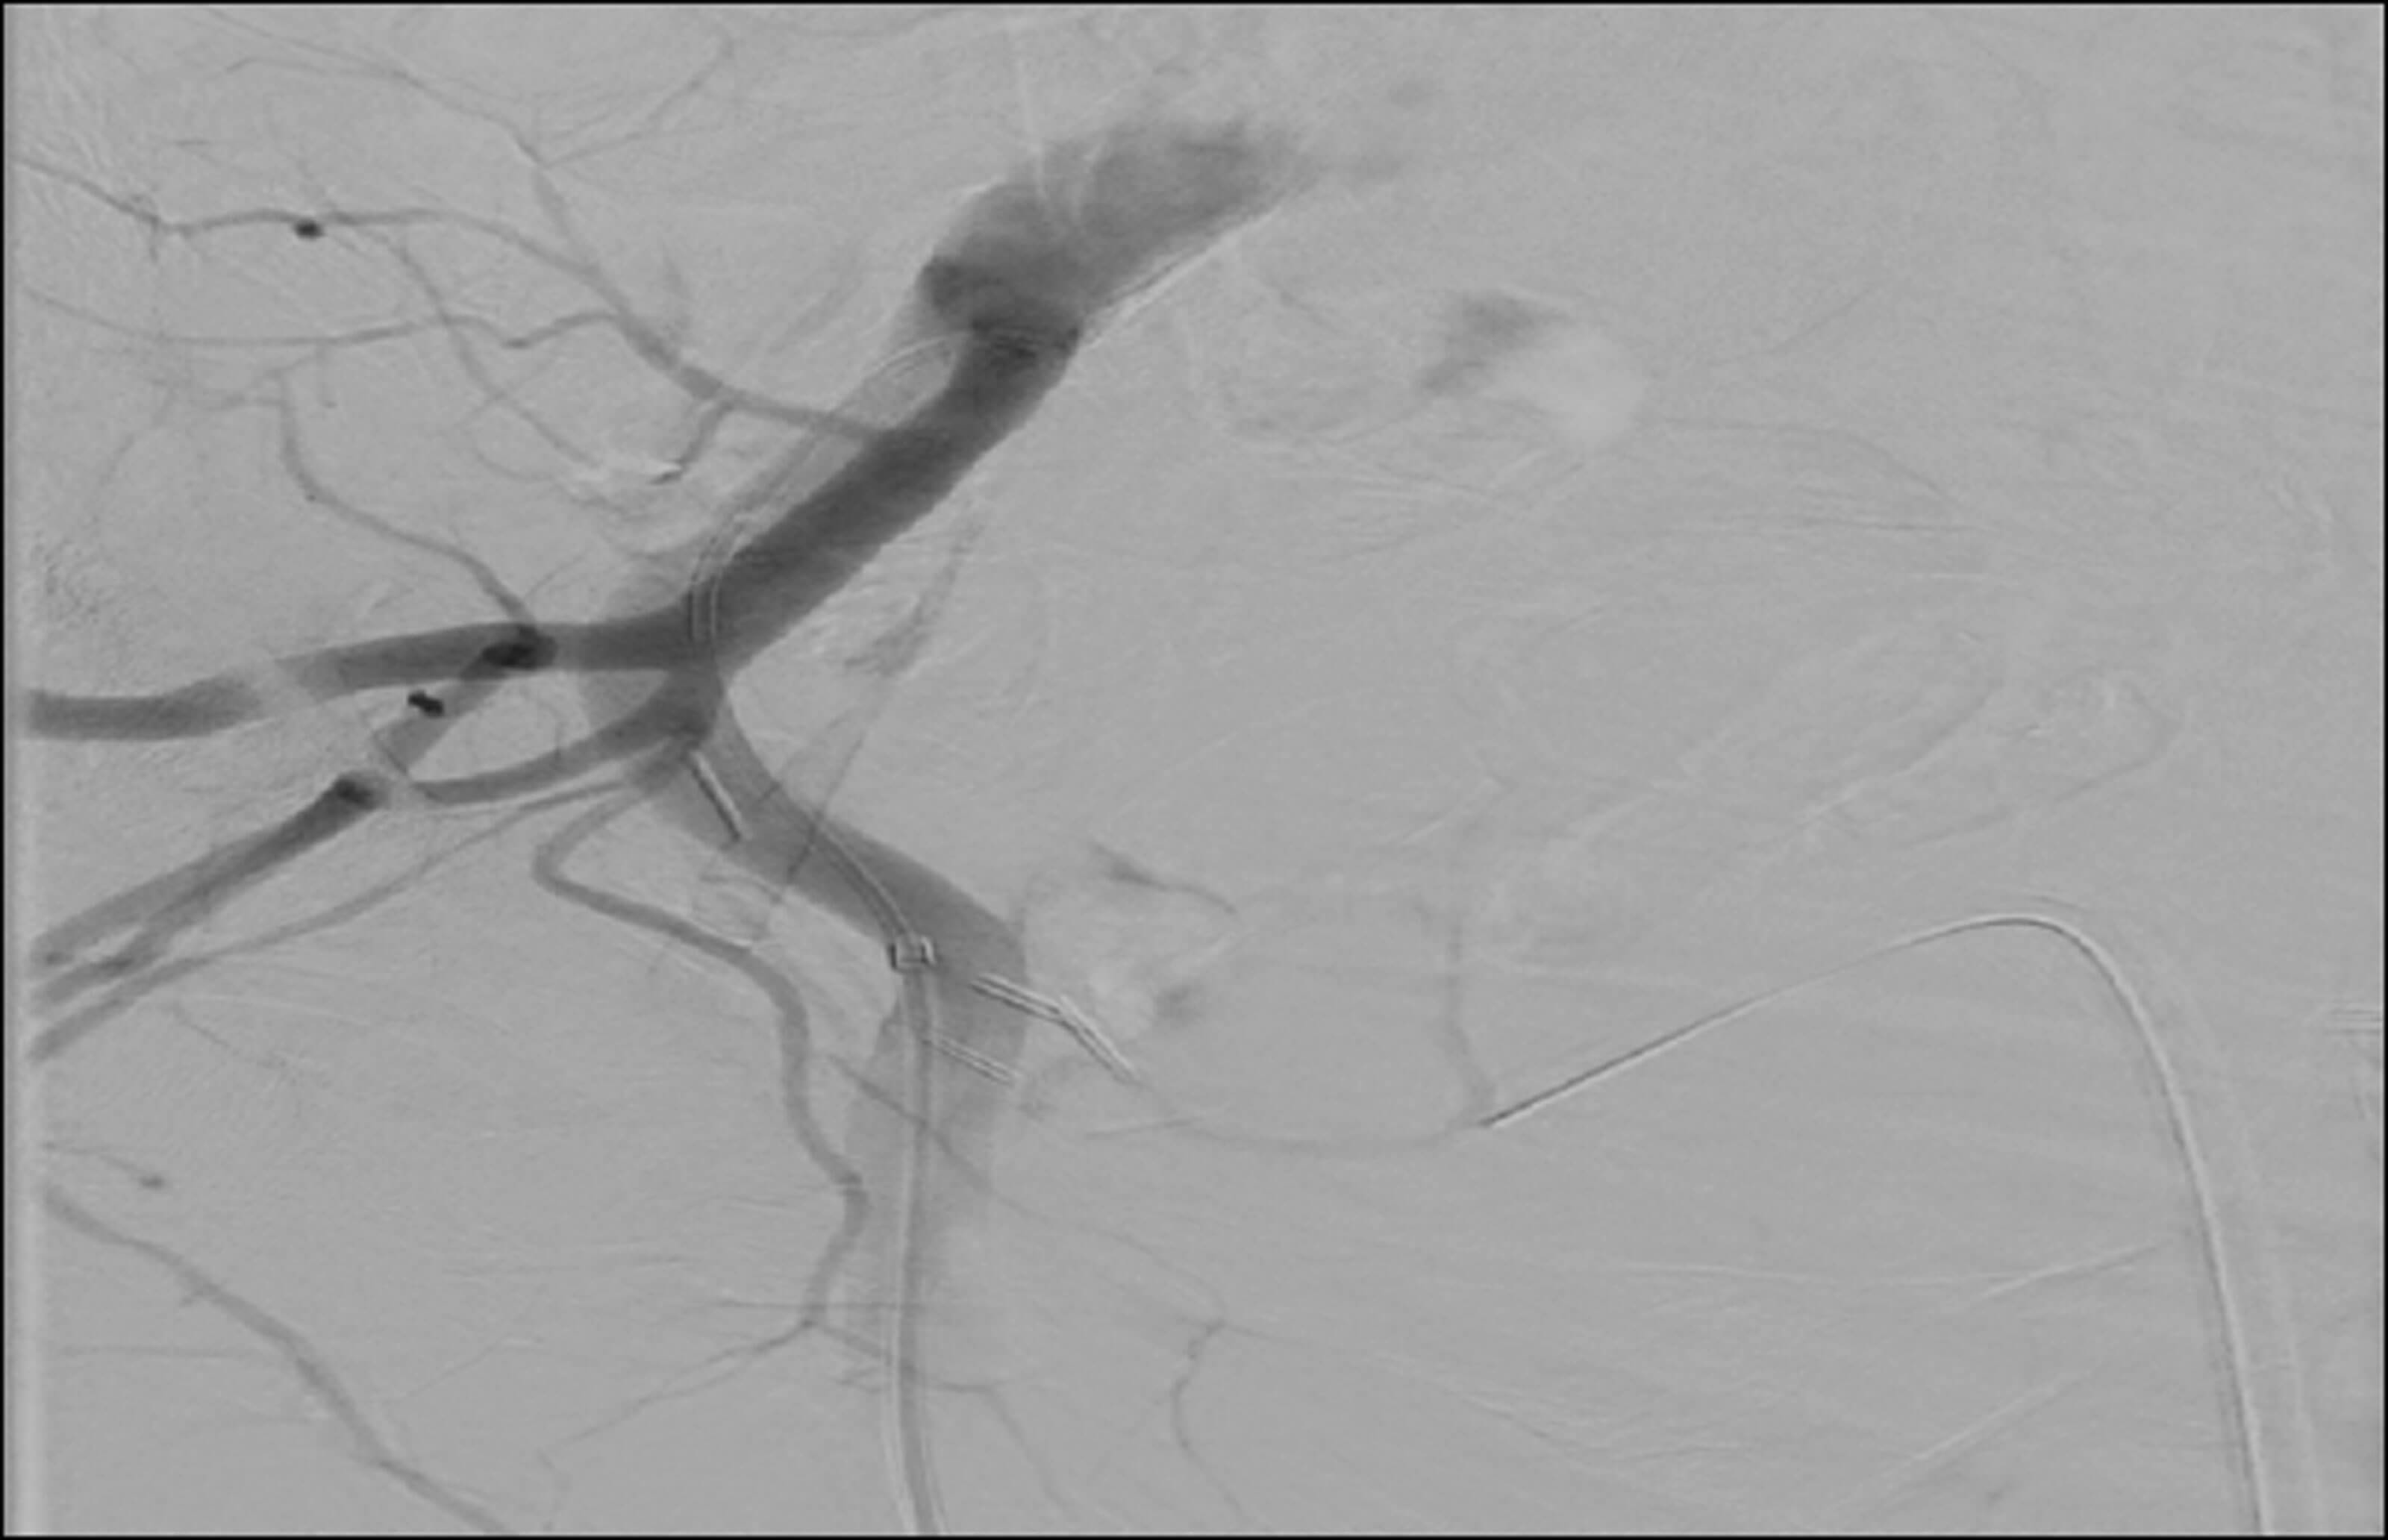

A 74-year-old male patient presented with visible haematuria and clot retention with a background of radical prostatectomy and salvage radiotherapy for a Gleason 9, T3b N1 M0 prostate cancer 13 years ago. The patient was managed for haemorrhagic radiation cystitis and was taken to theatre for bladder washes and diathermy twice but this had very little effect. Embolisation of bilateral superior vesical arteries was performed by interventional radiology (Figure 2). Post procedure, the patient recovered well and his haematuria settled prior to discharge.

Figure 2.